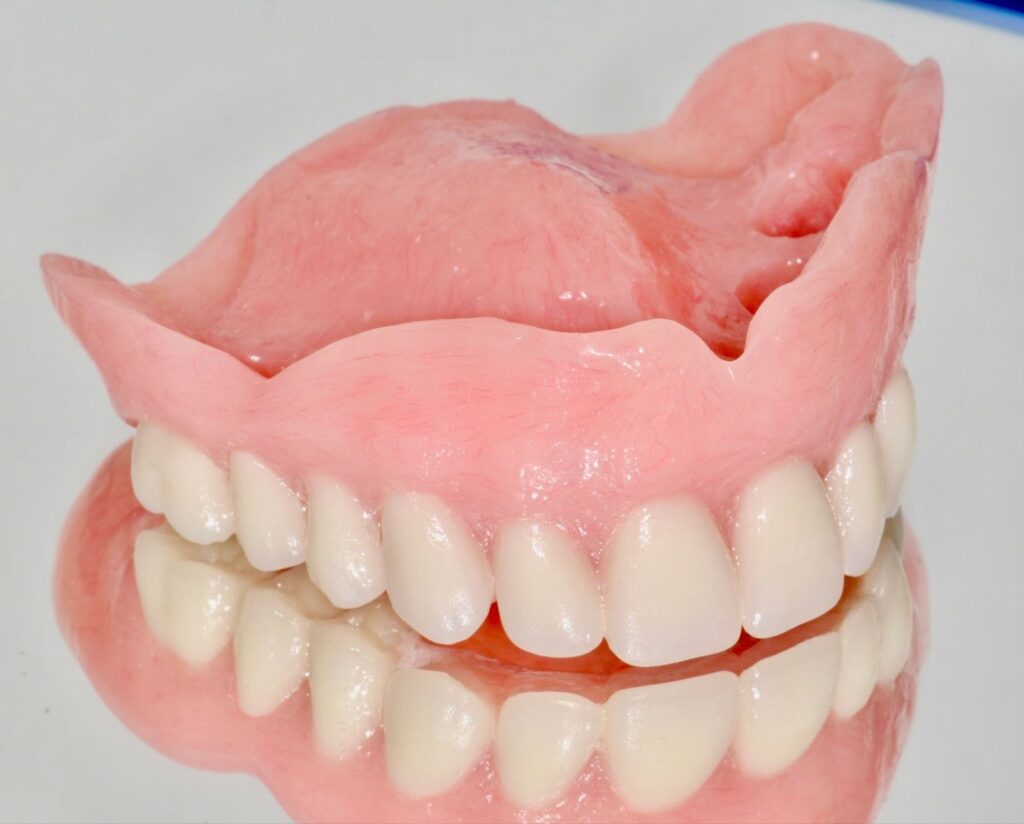

1. Complete Dentures

Complete dentures replace all teeth in the upper or lower jaw. These removable appliances rest on the gums and rely on suction and fit for stability.

Comfort level: Good with proper fit, but may feel less stable over time due to natural bone loss. Material: Acrylic Adhesive use: Sometimes required